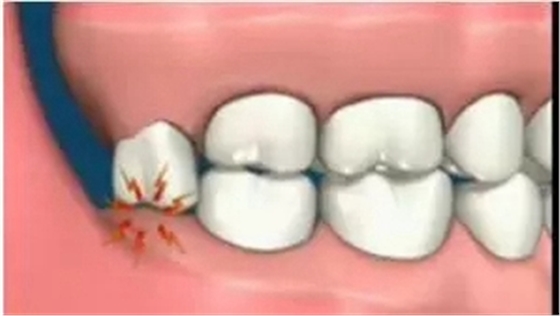

智齒萌出位置不正,即使沒有頂壞鄰牙,也可能與鄰牙形成間隙,產(chǎn)生局部的“衛(wèi)生死角”,食物殘渣和細菌堆積在這些部位,我們?nèi)粘K⒀篮茈y清潔到,久而久之就容易引發(fā)齲齒